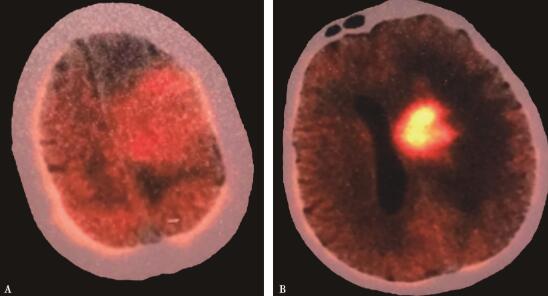

患者术后病理结果回报:(左额)不典型脑膜瘤(WHO Ⅱ级),免疫组化:EMA(+),VIM(+),stat6(-),PR(+),Ki-67(5%+),GFAP(-);(左额深部)恶性B细胞淋巴瘤,免疫组化:CD20(+),CD79a(+),Bcl2(+),Bcl6(部分+),CD3(-),Ki-67(70%+),PAX-5(+),CD10(-)。患者左额脑膜瘤和原发性中枢神经系统淋巴瘤(弥漫大B细胞型)诊断明确。患者术后一般状况可,遂先予甲泼尼龙激素治疗。患者术后复查头颅MRI提示淋巴瘤病灶较之前明显缩小(图4),继续予激素治疗,拟康复后转血液科行后续治疗。患者于术后第11天出现便血,停用激素并予支持对症处理后患者便血症状不能控制,反复消化道出血,于术后3周因“多脏器功能衰竭及消化道出血”宣告死亡。

图4 患者术后第二天复查头颅MRI提示左额深部病灶较术前明显缩小